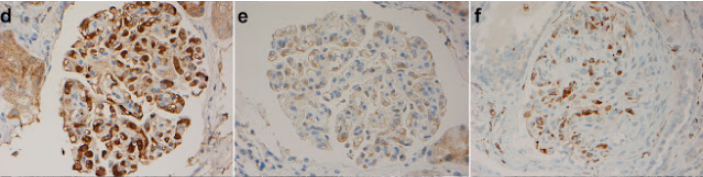

免疫蛍光染色ではびまん性の軽鎖沈着、IgG3陽性でκ鎖陽性である場合が多い。

|

メサンギウム領域や係蹄壁にIgG3に沈着する。

Am J Kidney Dis. 2016;67(3):e13-e15より引用 |

軽鎖ではκ優位に沈着